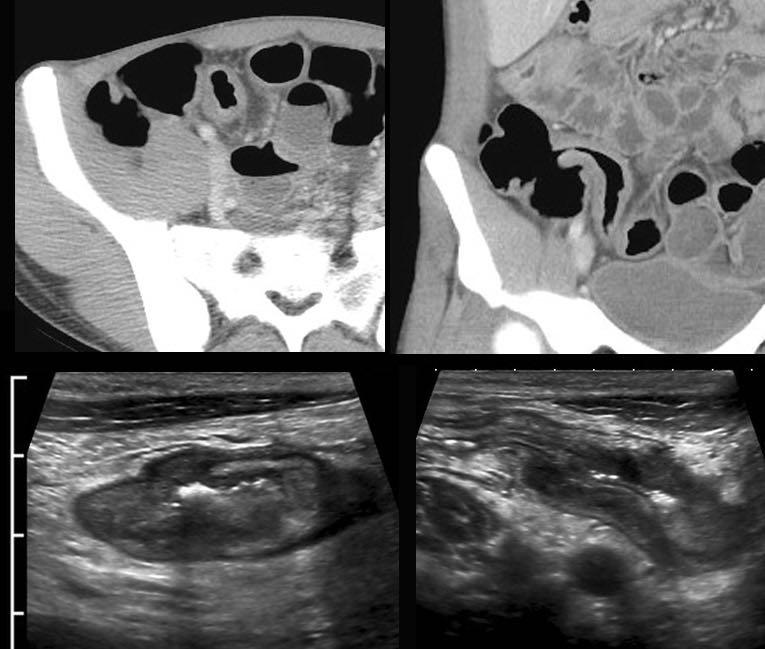

Áp xe

Hồi tràng tận đang viêm hoạt động với một vùng giảm âm có ranh giới vừa phải nằm ngoài thành ruột, được bao quanh bởi mô mỡ viêm, cho thấy sự hình thành đường xoang và áp xe.

Hai bệnh nhân có áp xe Crohn gần hồi tràng.

Lưu ý rằng áp xe trong bệnh Crohn thường nhỏ và xẹp.

Giải thích cho hiện tượng này là các áp xe này thường có thông nối hở với lòng hồi tràng, cho phép mủ thoát ngay vào lòng ruột khi áp lực tăng lên.